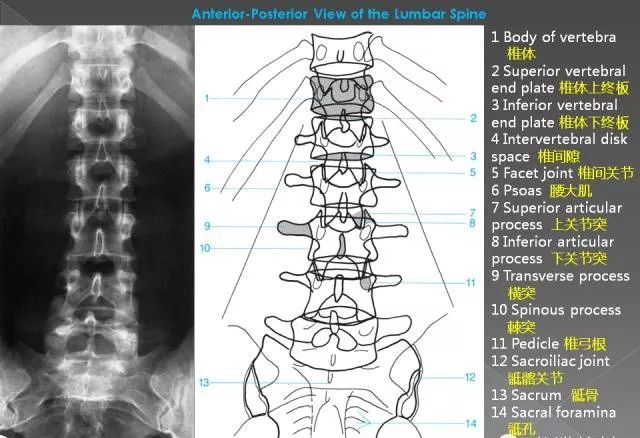

1、正位片

腰椎正位片,可显示腰椎有无侧凸,两侧横突大小有无异常(如第五腰椎横突肥大),有无移行椎(见后)、隐裂、棘突偏歪,椎间隙两侧是否等宽,椎弓根、关节突关节形状,椎弓根间距(椎管横径)大小等。

(1)腰椎棘突间联线一般均为一垂直线,如垂直线发生折曲或成角,提示椎体有移位现象。棘突偏歪曾被认为是椎间盘突出的体征。有人对此进行调查,发现一般腰椎X片和椎间盘突出腰椎X片相比,抛去侧突不计,两者无明显差异(分别为30.0%和31.3%),特别是常见的第五腰椎棘突扭曲,是发育的结果。

(2) 椎弓根形态和距离应留意,当一个椎体的椎弓根被压扁及椎弓根间距增宽时,常是椎管内神经纤维瘤的表现。关节突增大椎弓根间距小,应注意是否有退变性椎管狭窄。

(3)腰椎管横径的测量:通常测量两侧椎弓根断面内缘间最短距离作为椎管横径,此径平均值在正常人X线片自腰l至L5分别为24. 6mm,25.3mm,26.3mm,27.5mm,30.9mm,小于20mm者被认为是狭窄椎管,但其价值不如矢状径可靠。

(4)髂骨嵴间连线:在X线正位像上观察连接两侧髂骨嵴的横线与第4、5腰椎的关系。据认为髂嵴连线经L4椎体下部或其椎间盘为最稳固位置。横线与腰椎的关系结合其他参数可用以予测腰椎承受最大生物力学应力部位和退行性病变最可能发生的部位。

L4 L5之间容易发生退行性变的因素包括髂嵴间线位置过高,经过L4椎体上部;L5横突过大有移行脊椎现象。

L5骶l可能发生退行性变的因素有髂嵴横线经L5椎体和L5横突过短现象。

(5)还可观察两侧腰大肌阴影是否清晰。腰大肌阴影模糊、膨胀,常是腰大肌脓肿(结核)的表现。